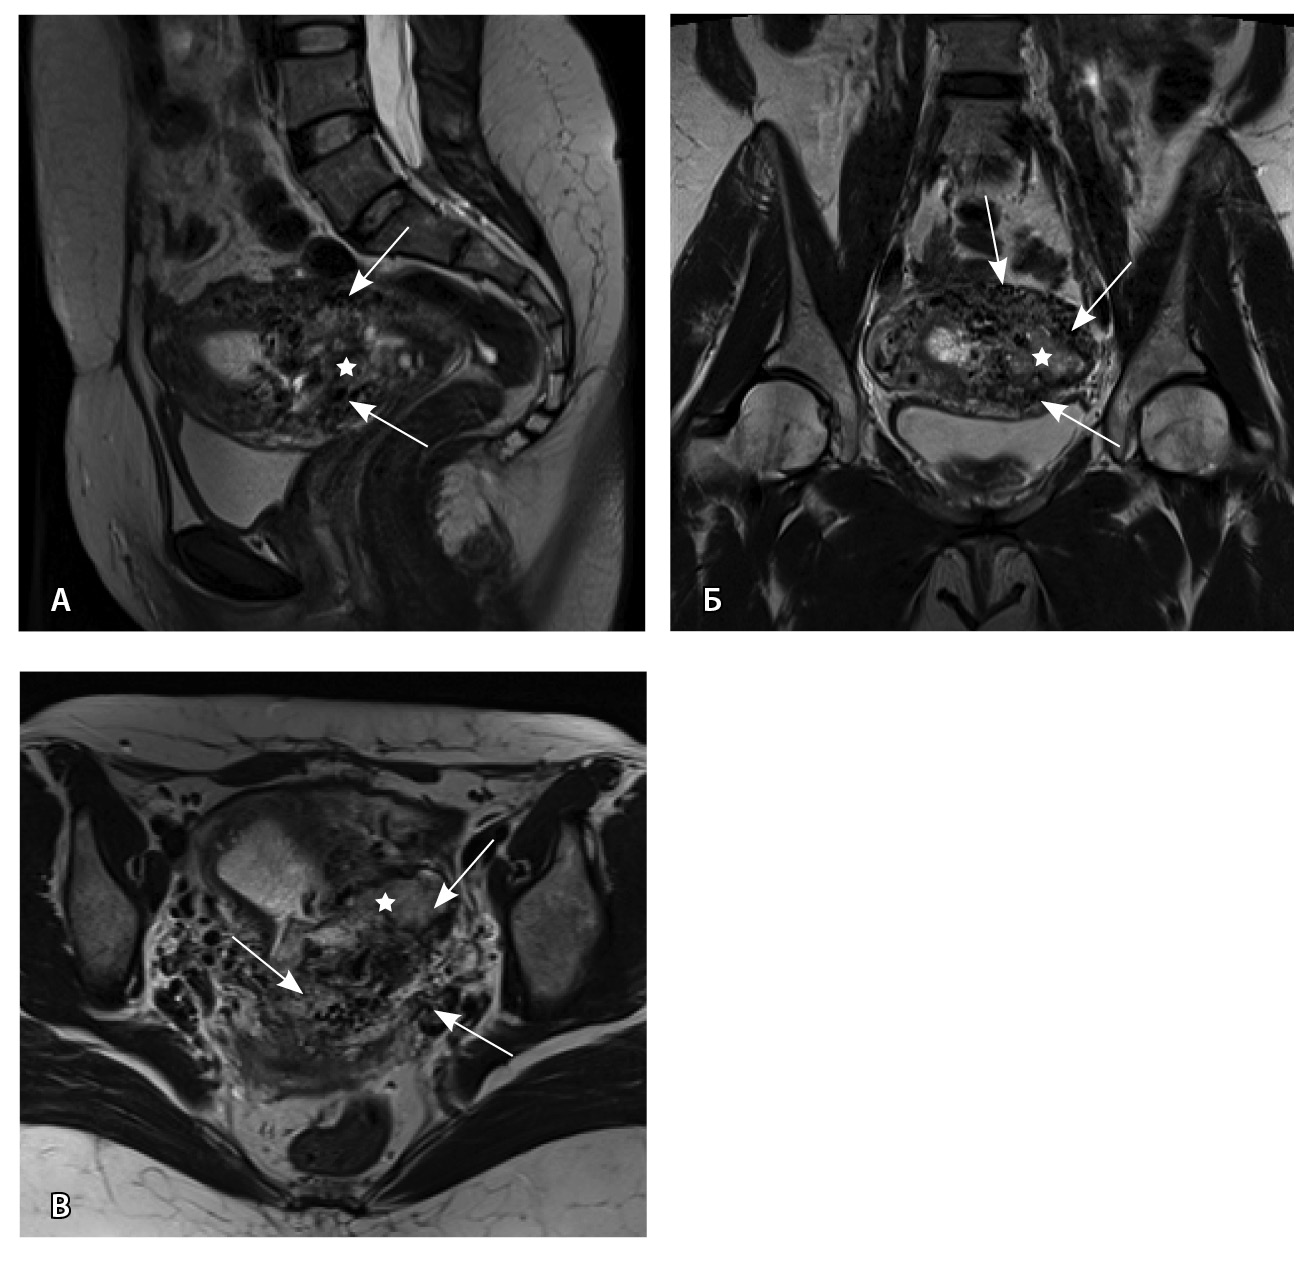

Пациентке выполнено МРТ-исследование на МР-томографе Siemens MAGNETOM Verio с индукцией магнитного поля 3T, с использованием стандартных катушек, в режимах Т1-взвешенного изображения (ВИ), Т2-ВИ, Т2-FS, FIESTA, DWI с получением изображений в сагиттальной, корональной и аксиальной плоскостях, динамическое внутривенное контрастирование (гадопентетовая кислота 0,2 мл/кг массы тела). Матка увеличена в размерах, с признаками снижения зональной дифференциации стенок, усиленным сосудистым компонентом, полость матки расширена с наличием примеси геморрагического содержимого, неравномерным утолщением эндометрия и пристеночными компонентами слизистой. В нижнем маточном сегменте определяется несостоятельный рубец от кесарева сечения, с наличием участка резко истонченной пролабирующей стенки матки слева и наличием дополнительного образования неоднородного сигнала, суммарно до 4,0 × 2,3 × 3,2 см, представленного фрагментами мягкотканного хориона (изоинтенсивного на Т2-ВИ), достигающего серозного покрова матки, и патологического сосудистого компонента в виде расширенных полнокровных сосудов, зон неоангиогенеза (рис. 1). На DWI признаков ограничения диффузии не определялось.

Рис. 1. Остатки вросшего хориона в несостоятельный рубец от кесарева сечения. Магнитно-резонансная томограмма, Т2-взвешенное изображение в сагиттальной (А), корональной (Б), аксиальной (В) плоскостях. Признаки наличия в проекции несостоятельного рубца от кесарева сечения фрагментов ткани вросшего хориона изоинтенсивного сигнала (отмечен звездочкой), с распространением до серозного покрова матки. Стрелками указаны гипоинтенсивные сосуды, зоны неоангиогенеза, артериовенозные сосудистые коллатерали

По наружной поверхности нижнего маточного сегмента и в параметрии определяется наличие полнокровной сосудистой сети с артериовенозными анастомозами. При контрастировании визуализируются фрагментарные участки гиперваскулярного накопления контраста вышеописанным образованием в рубцовой нише, а также определяется наличие артериовенозной сосудистой мальформации (рис. 2).

Рис. 2. Магнитно-резонансная томограмма, динамическое контрастное усиление в режиме Т1-взвешенного изображения FS. До контраста (А), в раннюю артериальную фазу (Б), паренхиматозную фазу (В), выделительную фазу (Г) определяются многочисленные патологические сосуды, зоны неоангиогенеза, сосудистые шунты как в стенке матки, так и в параметрии по типу артериовенозной мальформации